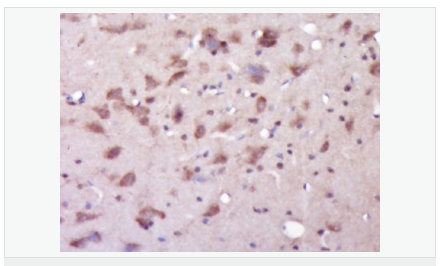

| 產(chǎn)品介紹 | Alzheimer's disease (AD) patients with an inherited form of the disease carry mutations in the presenilin proteins (PSEN1; PSEN2) or in the amyloid precursor protein (APP). These disease-linked mutations result in increased production of the longer form of amyloid-beta (main component of amyloid deposits found in AD brains). Presenilins are postulated to regulate APP processing through their effects on gamma-secretase, an enzyme that cleaves APP. Also, it is thought that the presenilins are involved in the cleavage of the Notch receptor, such that they either directly regulate gamma-secretase activity or themselves are protease enzymes. Several alternatively spliced transcript variants encoding different isoforms have been identified for this gene, the full-length nature of only some have been determined. [provided by RefSeq, Aug 2008] Function: Probable catalytic subunit of the gamma-secretase complex, an endoprotease complex that catalyzes the intramembrane cleavage of integral membrane proteins such as Notch receptors and APP (beta-amyloid precursor protein). Requires the other members of the gamma-secretase complex to have a protease activity. May play a role in intracellular signaling and gene expression or in linking chromatin to the nuclear membrane. Stimulates cell-cell adhesion though its association with the E-cadherin/catenin complex. Under conditions of apoptosis or calcium influx, cleaves E-cadherin promoting the disassembly of the E-cadherin/catenin complex and increasing the pool of cytoplasmic beta-catenin, thus negatively regulating Wnt signaling. May also play a role in hematopoiesis. Subunit: Homodimer. Component of the gamma-secretase complex, a complex composed of a presenilin homodimer (PSEN1 or PSEN2), nicastrin (NCSTN), APH1 (APH1A or APH1B) and PEN2. Such minimal complex is sufficient for secretase activity. Other components which are associated with the complex include SLC25A64, SLC5A7, PHB and PSEN1 isoform 3. Predominantly heterodimer of a N-terminal (NTF) and a C-terminal (CTF) endoproteolytical fragment. Associates with proteolytic processed C-terminal fragments C83 and C99 of the amyloid precursor protein (APP). Associates with NOTCH1. Associates with cadherin/catenin adhesion complexes through direct binding to CDH1 or CDH2. Interaction with CDH1 stabilizes the complex and stimulates cell-cell aggregation. Interaction with CDH2 is essential for trafficking of CDH2 from the endoplasmic reticulum to the plasma membrane. Interacts with CTNND2, CTNNB1, HERPUD1, FLNA, FLNB, MTCH1, PKP4 and PARL. Interacts through its N-terminus with isoform 3 of GFAP. Interacts with DOCK3. Subcellular Location: Endoplasmic reticulum membrane; Multi-pass membrane protein. Golgi apparatus membrane; Multi-pass membrane protein. Cell surface. Note=Bound to NOTCH1 also at the cell surface. Colocalizes with CDH1/2 at sites of cell-cell contact. Colocalizes with CTNNB1 in the endoplasmic reticulum and the proximity of the plasma membrane. Also present in azurophil granules of neutrophils. Tissue Specificity: Expressed in a wide range of tissues including various regions of the brain, liver, spleen and lymph nodes. Post-translational modifications: Heterogeneous proteolytic processing generates N-terminal (NTF) and C-terminal (CTF) fragments of approximately 35 and 20 kDa, respectively. During apoptosis, the C-terminal fragment (CTF) is further cleaved by caspase-3 to produce the fragment, PS1-CTF12. After endoproteolysis, the C-terminal fragment (CTF) is phosphorylated on serine residues by PKA and/or PKC. Phosphorylation on Ser-346 inhibits endoproteolysis. DISEASE: Defects in PSEN1 are a cause of Alzheimer disease type 3 (AD3) [MIM:607822]. AD3 is a familial early-onset form of Alzheimer disease. Alzheimer disease is a neurodegenerative disorder characterized by progressive dementia, loss of cognitive abilities, and deposition of fibrillar amyloid proteins as intraneuronal neurofibrillary tangles, extracellular amyloid plaques and vascular amyloid deposits. The major constituent of these plaques is the neurotoxic amyloid-beta-APP 40-42 peptide (s), derived proteolytically from the transmembrane precursor protein APP by sequential secretase processing. The cytotoxic C-terminal fragments (CTFs) and the caspase-cleaved products such as C31 derived from APP, are also implicated in neuronal death. Defects in PSEN1 are a cause of frontotemporal dementia (FTD) [MIM:600274]. Similarity: Belongs to the peptidase A22A family. SWISS: P49768 Gene ID: 5663 Database links: Entrez Gene: 5663 Human Entrez Gene: 19164 Mouse Omim: 104311 Human SwissProt: P49768 Human SwissProt: P49769 Mouse Unigene: 3260 Human Unigene: 998 Mouse Unigene: 44440 Rat Important Note: This product as supplied is intended for research use only, not for use in human, therapeutic or diagnostic applications. 此抗體識別分子量為45-50kDa早老素蛋白-1。PS-1主要在神經(jīng)細胞中表達,早老蛋白集中于體細胞和樹(shù)突狀細胞中。相反,再早發(fā)家族AD(FAD)中和散發(fā)AD病人中,PS1免疫反應出現在老年斑和神經(jīng)纖維纏結的神經(jīng)炎中。 |